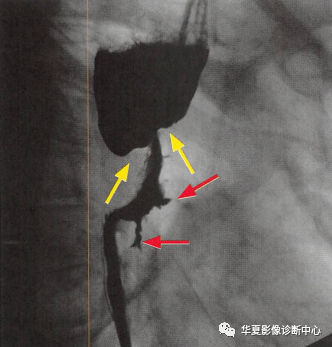

黑色玫瑰征,你知道嗎?

食管癌在鋇餐造影下的一種表現(xiàn)之一,顯示食管局部不規(guī)則狹窄(黃箭頭:玫瑰花花干),近端食管擴(kuò)張(萎陷的玫瑰花朵),兩個(gè)不規(guī)則線狀潰瘍(紅箭頭:玫瑰花葉/刺),形似黑色玫瑰花,小編原創(chuàng)命名為:“黑色玫瑰花征”,幫助記憶,加深映像&食管癌表現(xiàn)多樣。 早期食管癌在鋇餐中可能表現(xiàn)為斑塊樣或息肉樣病變,也可以呈食管壁的局灶性不規(guī)整。 進(jìn)展期食管癌